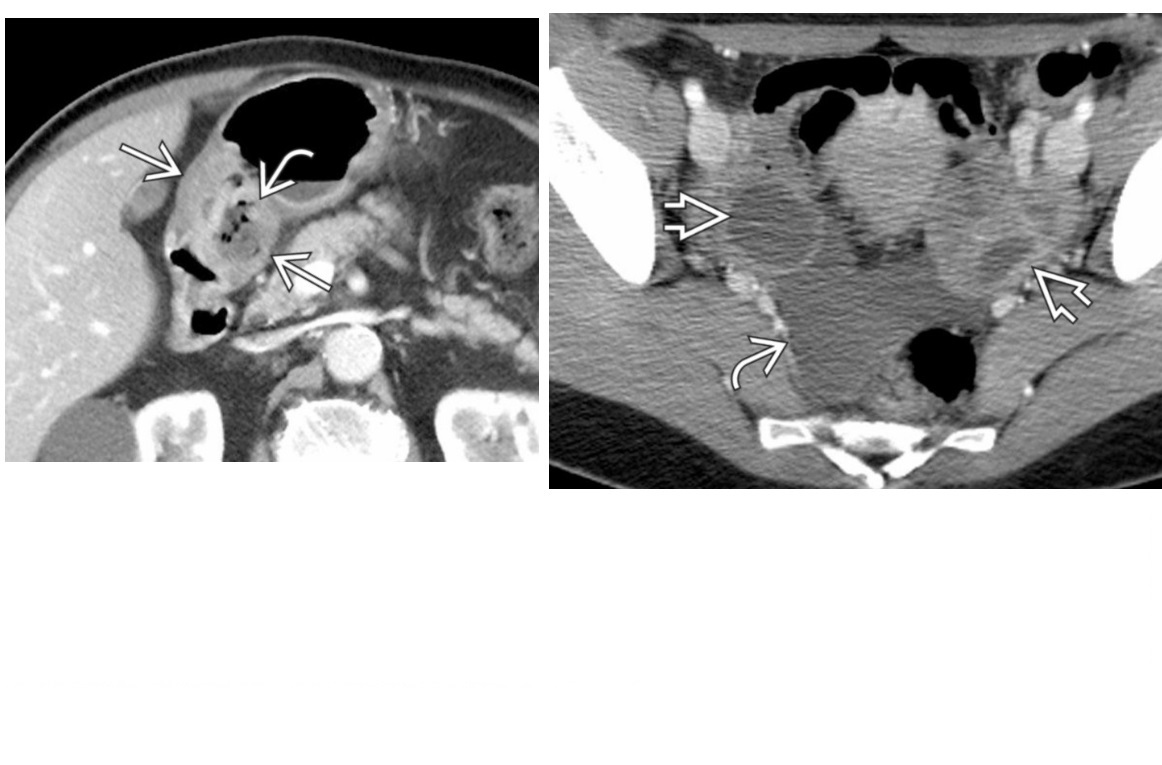

Carcinoid

spiculated mesenteric mass with calcification/ desmoplastic reaction

Tethering of SB loops

90% arise in terminal ileum/appendix

Hyper-vascular liver mets - Carcinoid syndrome

111I- Octreotide scans (1st - highest sensitivity)

or 123I-MIBG (for 10% dont take up octreotide)

for Dx and staging

Big centres use gallium PET

Assocaited with MEN 1 or MEN 2a